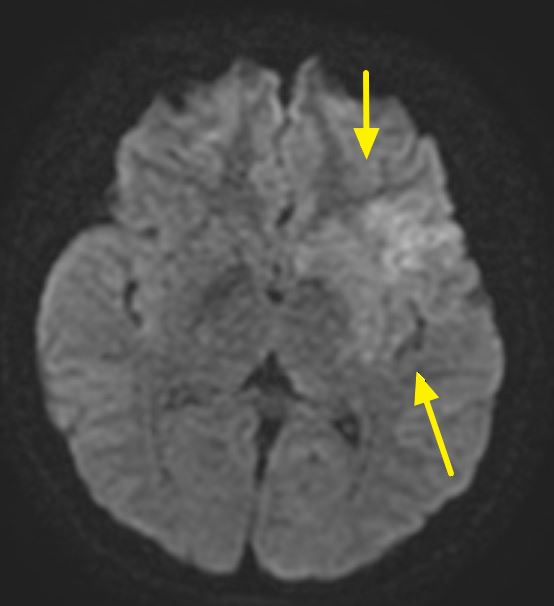

郭葉璘說明,左側大腦掌管語言中樞、身體右側活動能力及視覺與空間感知區域,中大腦動脈是負責供應大腦3分之2的重要血流。磁振造影中的擴散權重影像序列(DWI),能在中風發生後30分鐘內偵測腦部受損區域。檢查顯示該學生的左側中大腦動脈完全阻塞,磁振中的擴散權重影像序列也出現一塊淡淡的受損區域,表示阻塞的危險性正快速提高中。若不即時處理,這片受損區域會持續擴大,腦部將因血栓壓迫而腫脹,同時往下壓迫腦幹,危及呼吸與心跳中樞,甚至造成生命危險。